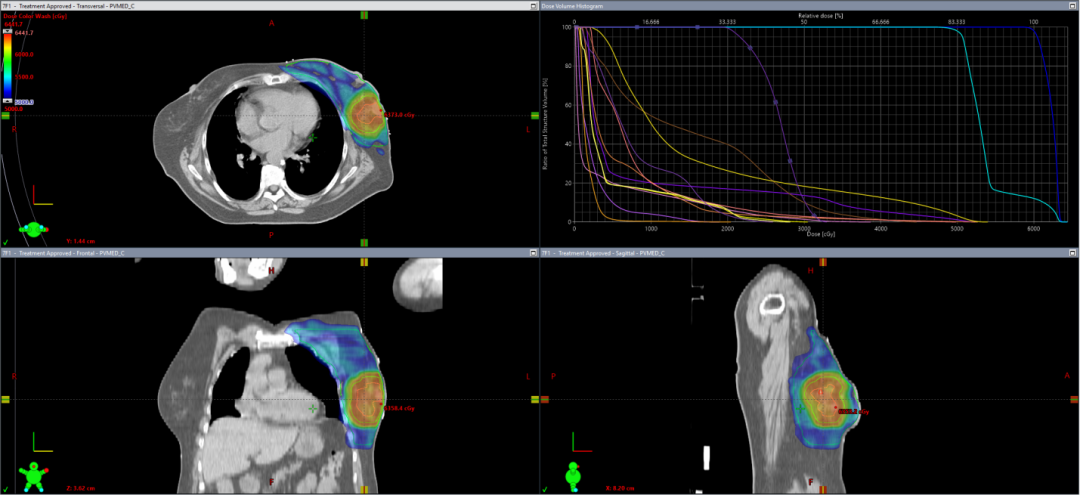

近日,中山大学附属第三医院放疗科收治一例特殊乳腺癌病例。该患者于乳腺癌根治术后五年即出现局部复发,不仅需承受二次手术带来的身心创伤及经济负担,更面临肿瘤侵袭性增强导致的远处转移风险显著升高。经深入追溯治疗史发现,该患者术后未遵医嘱严格执行术后辅助放射治疗,这一关键治疗环节的缺失与本次肿瘤复发存在明确相关性。放疗作为乳腺癌治疗的核心手段之一,通过高能射线精准杀灭残留癌细胞,降低复发风险。尤其对于保乳术后患者,放疗是必做的一个环节,能将局部复发率从30%降低至5%以下。 哪些乳腺癌患者需要放疗? 放疗适应证需结合病情精准判断,主要包含以下情况: 1、保乳术后患者:原则上均需全乳放疗,但70岁以上、肿瘤≤2cm且激素受体阳性的低危患者可豁免放疗。 2、乳房全切术后高危患者: 1)肿瘤≥5cm或侵犯胸壁/皮肤; 2)腋窝淋巴结转移阳性。 3、复发或转移患者:骨转移及脑转移、全身远处转移等均可姑息性放疗甚至根治性放疗,显著提升生存质量,延长生命。 技术革新:从精准放疗到器官保护 在徐向英主任严格要求及乳腺癌诊疗指引下,中山三院肿瘤放疗科从放疗体位固定、CT模拟定位开始,到靶区勾画、放疗计划设计及验证,再到放疗实施上,每一步都坚守“团结协作、规范创新”的学科理念。 1、体位固定阶段:采用发泡胶、真空垫、体膜等标准的固定装置,实现放疗期间体位保持高一致性。 2、放疗计划阶段:采用调强适形放疗(IMRT),通过精准勾画靶区、设计放疗计划,实现精准放疗,同时通过严格限制重要危及器官的靶区受量,着重保护患者的心脏、肺等重要器官。 3、放疗实施阶段:每次放疗前都通过CBCT技术,监控靶区、器官位置并精准匹配照射区域;目前已推进光学体表监测技术的引入,通过实时追踪呼吸运动,进一步将放疗体位误差控制在毫米级。 图1放疗体位固定装置 图2 放疗实施过程 图3 假体/扩张器植入术后放疗TPS图 图4 保乳术后放疗TPS图 图5 改良根治术后放疗TPS图 图6 CBCT技术精准匹配 乳腺癌放疗全流程中的人文关怀 1、隐私与操作规范:增加女性技师操作,严格“一出一入”制度,确保隐私保护。 2、皮肤护理要点: 1)照射区皮肤避免摩擦(禁胶布、抓挠),可涂医生推荐保护剂(如三乙醇胺乳膏)。 2)穿宽松V领棉质衣物,避免胸罩/饰品;清洁用温水,禁用香皂/化妆品。 3)防晒、防冷热刺激,禁止泡澡/游泳。 3、健康管理建议: 1)每日患侧手臂功能训练(爬墙、外展等),避免负重或下垂,多叉腰保持腋窝干燥。 2)加强营养,适度运动,规律作息。 乳腺癌放疗中常见副作用及应对措施 1、皮肤反应:分级管理,从轻度发红到破溃渗液,需按医嘱使用药物或敷料。注意:放疗结束后2-3周仍需持续护理,直至皮肤愈合。 2、黏膜损伤:口腔黏膜保护:加强漱口,避免过热或坚硬食物;咽痛时可药物治疗。 3、疲劳与血象监测:尤其是同步使用其他抗肿瘤药物(靶向药、内分泌药等)的患者,建议每周复查血常规,及时处理白细胞降低等问题。 突破认知误区:这些传言不可信! 1、“放疗会传染”:外照射治疗后体内无放射性残留,可安全接触家人。 2、“心脏受损不可避免”:精准放疗及器官保护等先进技术的支持下,患者可长期生存,心脏毒性可防可控。 3、“必须剃光腋毛”:仅需清洁皮肤,除非毛发影响定位标记。 中山三院放疗科在国内著名放疗专家徐向英主任的带领下,团队始终秉持“团结协作、规范创新”的理念,以"精准放疗"为核心,融合先进技术与严格质控,实现乳腺癌放疗"高能低毒";同时创新人文关怀模式,通过隐私保护、心理支持等举措,让患者在规范治疗中保有尊严与生活质量,真正践行"疗效与温情并重"的医疗理念。 科室简介 学科理念: “团结协作 规范创新” 中山三院肿瘤放射治疗科公众号 学科特色 科室创建于2018年3月,由中山大学引进的国内知名放射肿瘤学专家徐向英教授担任学科创始人及首任科主任。科室由肿瘤放疗病区、肿瘤放疗中心两大部门组成,目前病区拥有床位36张。 专科特色为肺部小结节及早期肺癌影像学诊断、脑胶质瘤、鼻咽癌及头颈部肿瘤、肺癌、乳腺癌、食管癌、肝癌、妇科肿瘤、前列腺癌、直肠癌等的精准放射治疗、放化疗及免疫综合治疗。 岗位结构多样,主要由医师、护师、物理师、技师等岗位组成。 人才队伍 目前学科工作人员共36人,医师9人(教授1人,主任医师1人、副主任医师2人、主治医师1人及住院医师5人);护士12人(主管护师3人);物理师4 人(中级职称2人);技师9人;文员1人;辅助人员1人;团队中博士6人,硕士6人,博士后导师1人。 放疗设备 实现技术 可完成立体定向放疗(SBRT)或体部立体消融放疗(SABR)、容积调强放疗(VMAT)、图像引导放疗(IGRT)、调强放疗(IMRT) 及三维适形放疗(3DCRT)等多种精准放疗技术,能够做到高精度、高剂量、高疗效和低损伤。目前,大部分患者放射治疗误差范围可控制在1mm以内,另外中山三院肿瘤放射治疗科所有盆腔患者(宫颈癌、子宫内膜癌、前列腺癌及直肠癌等)治疗全程进行膀胱超声尿量控制,确保患者治疗位置的精准性及重复性,为癌症患者提供强大的精准放射治疗设备支撑和技术保障。